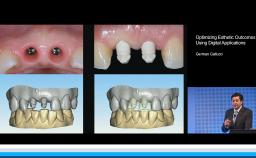

Treatment Outcomes and Continuing Care

Complications in Regeneration and Reconstruction